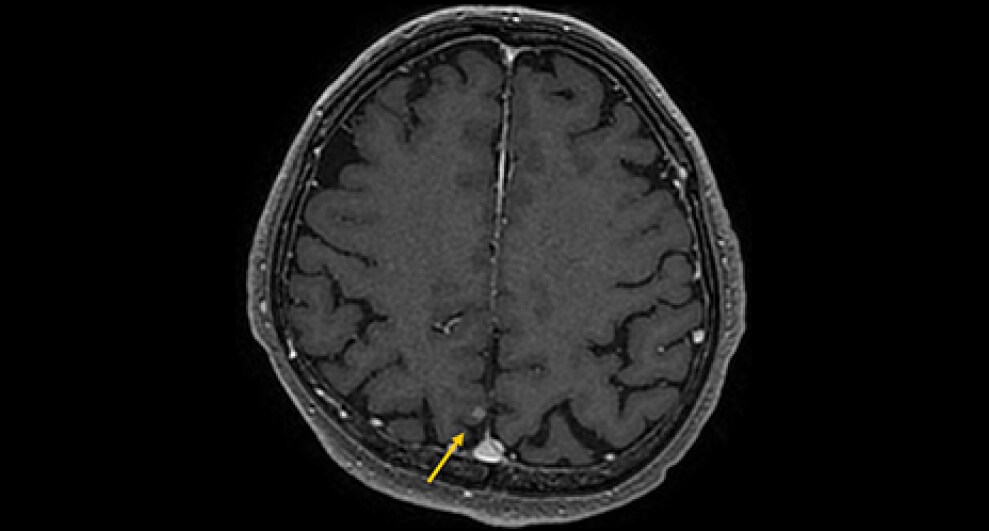

症例は70歳代男性。物が二重に見える、ふらつくとの訴えで来院。非造影MRIにて脳幹部や小脳に4個の多発脳腫瘍が認められ、症状と合致した。全身精査にて進行胃癌が発見され、その脳転移と診断された。放射線治療の適応判定のため造影MRIを施行し、新たに大脳に3個の微小転移が同定された。病変のサイズ・分布から微小転移を含む7個の腫瘍に対して定位放射線治療が可能と判断され、速やかに治療導入に至った。

本症例では先行する非造影MRIにて右中脳や左小脳の多発腫瘤が指摘され、周囲に浮腫を伴うことから転移が疑われていたが、病変数や大きさ・範囲ははっきりしなかった。造影MRIを実施することにより、右中脳に1個、左小脳に3個の2㎝大の輪郭の明瞭な腫瘍が確認されたほか、1㎝未満の3個の微小病変を新たに検出できた。非造影MRIを見直したところ7㎜の結節はFLAIRでも淡い高信号を示していたが質的診断は困難であった。3㎜の病変は非造影MRIでは存在診断不能であった。微小病変のうち2個は高位前頭葉の機能的に重要な部位に位置しており、治療適応と考えられた。造影MRIにより腫瘍の正確な個数とサイズ、分布の正確な情報を確認した後、定位放射線治療が可能と判断され、3D-FSPGR画像を治療計画に利用して迅速に治療が開始された。